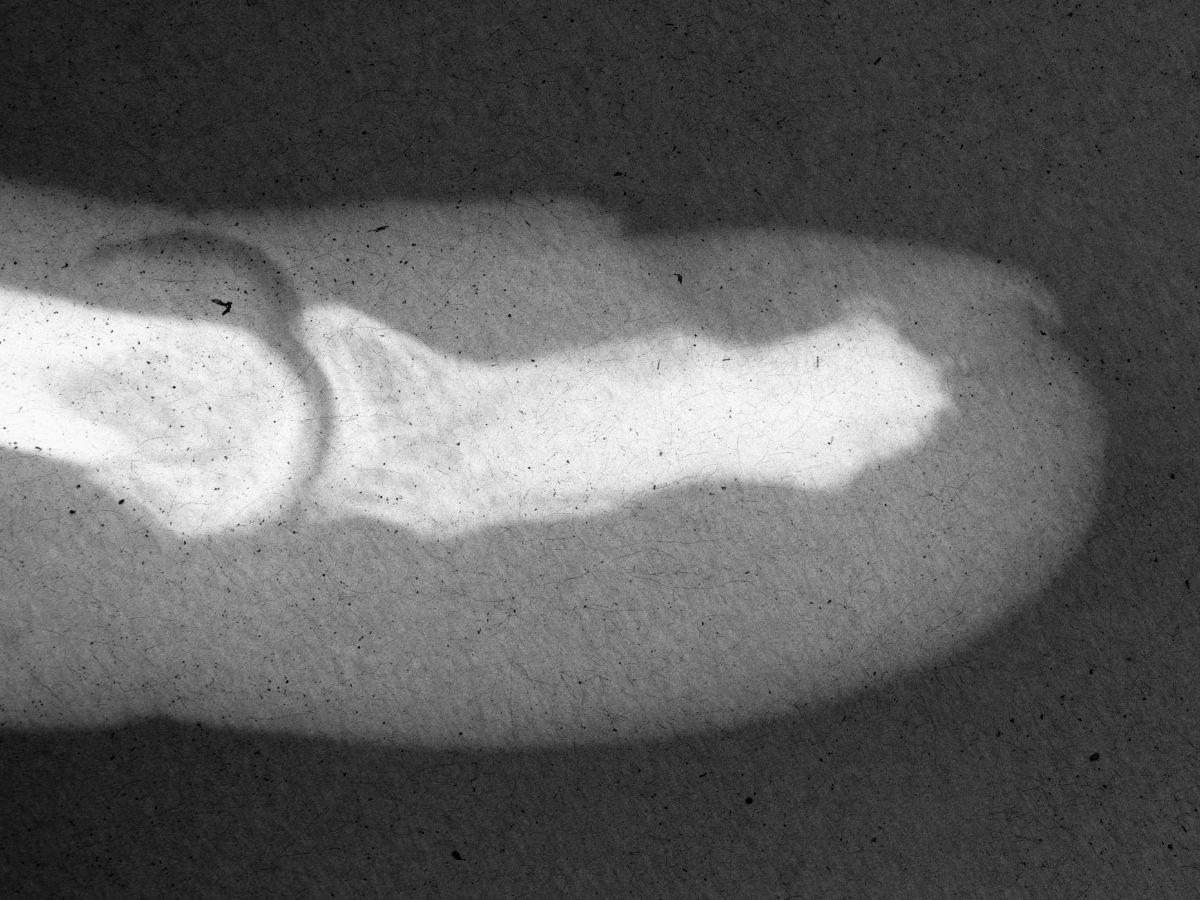

| A typical whitish smooth epidermal inclusion cyst was found protruding from the tuft of the distal phalanx. |

| The cyst was excised, and the cavity was debrided with a high speed burr. |